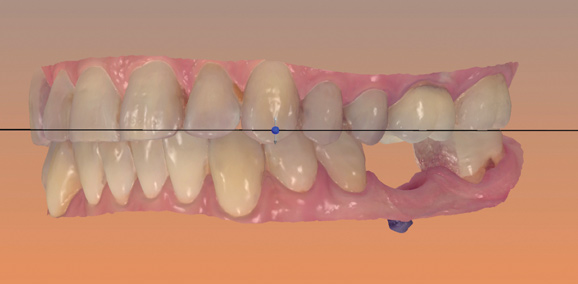

Fig 12. Virtual planning of a posterior implant (Fig 12) resulted in inadequate restorative running room for the crown emergence profile in the cross-sectional CBCT image. Revision (Fig 13) resulted in deeper positioning of the implant for restorative running room but necessitated transcrestal sinus elevation, possibly with the addition of bone via the osteotomy to tent the membrane.

Figure 12

Fig 13. Virtual planning of a posterior implant (Fig 12) resulted in inadequate restorative running room for the crown emergence profile in the cross-sectional CBCT image. Revision (Fig 13) resulted in deeper positioning of the implant for restorative running room but necessitated transcrestal sinus elevation, possibly with the addition of bone via the osteotomy to tent the membrane.

Figure 13

The direct impact of this collaborative approach is that the team is better able to anticipate surgical challenges and preplanned solutions. For instance, whether bone grafting relative to implant placement will be required and how to achieve these augmentation goals can be anticipated (Figure 12 and Figure 13). Planning implant position from the restoration down may allow positioning implants for screw retention or angled-screw technology, thus minimizing the need for cemented restorations. This type of preview may influence the choice of implant for the desired restoration, as not all systems currently offer corrective screw technologies without migrating into the use of non-authentic components.